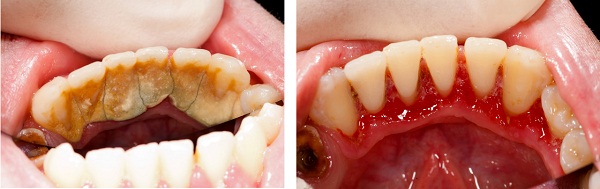

一、 你的牙結石到了哪一級?別等牙齦出血才重視

牙結石,其實是牙菌斑鈣化後的產物。如果日常刷牙清潔不到位,食物殘渣與細菌形成的軟垢會在唾液中礦物質的作用下逐漸變硬,形成緊緊附著在牙齒上的結石 。

牙結石的形成通常在24至72小時內即可發生,且一旦形成,日常刷牙根本無法去除 。根據牙結石的量和覆蓋范圍,臨床上通常將其分為以下幾個等級,你可以對照自查:

·0度:無軟垢及牙結石,這是理想的口腔狀態 。

·1度:少許軟垢或牙結石,附著未超過牙面的1/3。此時通常無明顯症狀,但需要注意清潔 。

·2度:有可見的牙結石,未超過冠面的1/3,可能伴有少量齦下結石。此時可能伴有偶爾的牙齦出血 。

·3度:牙結石不超過冠面的2/3,伴有較多的齦下結石。此時往往伴隨明顯的牙齦紅腫、萎縮、持續性口臭,甚至牙齒松動 。

牙結石的多孔結構極易吸收細菌毒素,不僅壓迫牙齦,更是導致牙齦炎、牙周炎,從而引起牙齒松動脫落的元凶 。因此,定期通過專業醫療手段清除牙結石,是維護牙周健康不可或缺的一環。